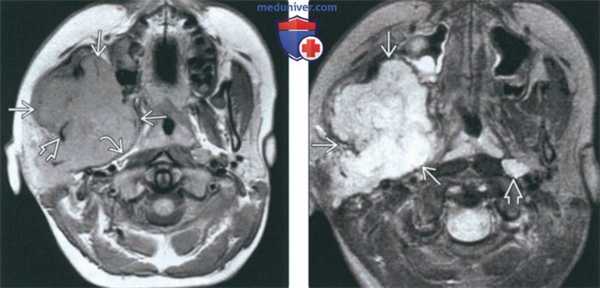

(Слева) МРТ Т1ВИ FS с КУ, аксиальная проекция. Лейомиосаркома жевательного пространства высокой степени злокачественности. Опухоль неоднородно накапливает контраст и прорастает в нижнюю челюсть. Только по данным лучевой диагностики дифференцировать различные типы сарком невозможно, за исключением случаев обнаружения матрикса остео- или хондросаркомы.

(Справа) МРТ Т1ВИ FS с КУ, коронарная проекция, тот же пациент. Новообразование, накапливающее контраст, распространяется в полость черепа через овальное отверстие. Отсюда опухоль может прорастать в пещеристый синус.

(Слева) На аксиальной МРТ (Т1 ВИ C+) в жевательном пространстве визуализируется лейомиосаркома высокой степени злокачественности, неравномерно накапливающая контраст и поражающая нижнюю челюсть. Большинство типов сарком жевательного пространства сложно дифференцировать в отсутствие костного или хондроидного матрикса.

(Справа) На корональной МРТ (Т1 ВИ С+ FS) у этого же пациента визуализируется контрастирующаяся опухоль с интракраниальным распространением через овальное отверстие а и поражением кавернозного синуса.